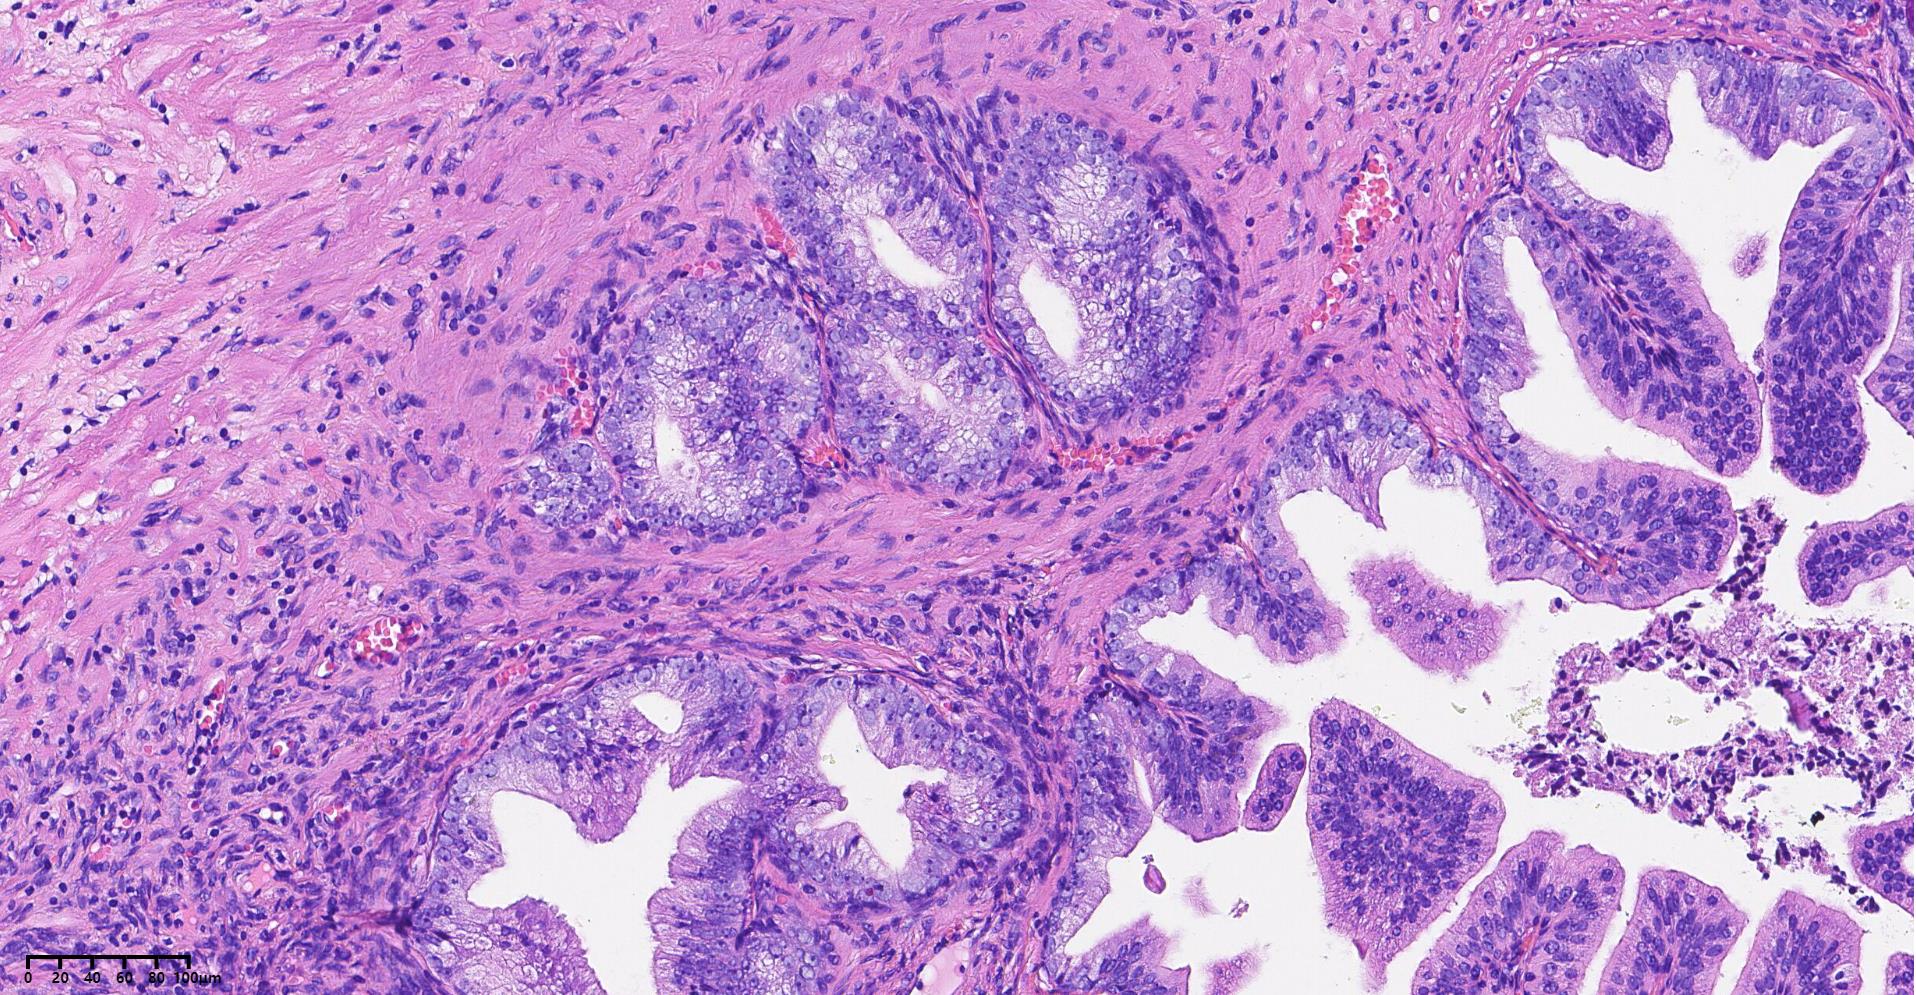

前列腺PIN?

性别

男

年龄

79岁

临床诊断

一般病史

发现肉眼血尿5月余,PAS 5.7

标本名称

经尿道前列腺等离子电切组织

大体所见

碎软组织一堆,共直径5.2

BPH.

本例核仁巨大,值得关注!

嗜酸性大核仁,胞浆透亮,PIN没问题。还是组化一下吧,